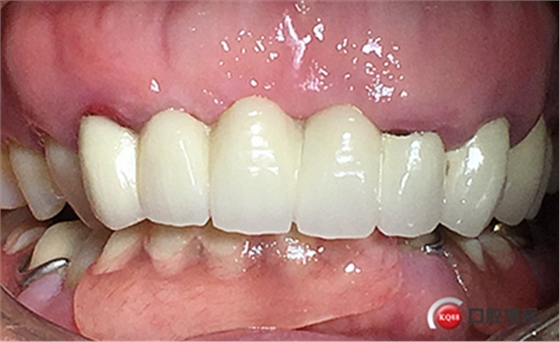

戴牙。

戴牙后半年復(fù)查。